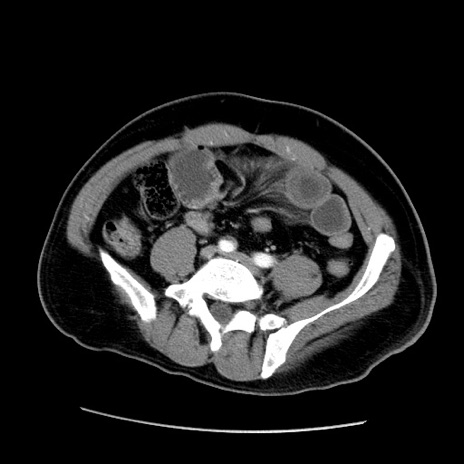

症例22(横断像)

【症例】50歳代男性

【主訴】腹痛

【現病歴】AVMからの被殻出血のため回復期リハ病棟入院中。 本日午後3時頃急に下腹部痛が出現した。

【既往歴】AVM、被殻出血、虫垂炎、高血圧

【身体所見】意識晴明、左半身不全麻痺、会話の理解は良好、36.5°C、腹部:膨隆、全体に板状硬、下腹部正中に圧痛点あり、反跳痛-、筋性防御不明、右下腹部にope scar

【データ】WBC 9400、CRP 0.06